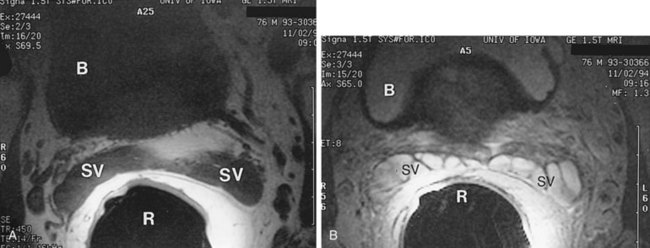

MRI is another useful imaging modality for the seminal vesicles, which gives more anatomic detail than CT. On T2-weighted images, the ampulla of the vas deferens is visible approximately 71% of the time and exhibits low signal intensity. The seminal vesicles exhibit high signal intensity 79% of the time, low signal intensity 19% of the time, and a heterogeneous signal intensity 2% of the time on T2-weighted images (Roy et al, 1993). On T2-weighted images, the seminal vesicles generally have similar or higher intensity than fat in patients less than 70 years of age, and typically have signal intensity lower than that of fat in patients greater than 70 years of age. The convolutions of the seminal vesicles can be seen on T1-weighted imaging with contrast (Fig. 37–20) (Secaf et al, 1991).

Figure 37–20 Transaxial MRI of normal seminal vesicles (SV) with endorectal coli. A, T1-weighted image. B, T2-weighted image. B, bladder; R, rectum.

On MRI, seminal vesicle agenesis is best exemplified on T1-weighted axial images (Fig. 37–21). Care must be taken to not mistake the vesicoprostatic venous plexus for small glands. Arteriovenous malformations appear as large ectatic vessels adjacent to the lateral edge of the seminal vesicle. After androgen ablation, seminal vesicles demonstrate low signal intensity on T2-weighted images and appear small in size (Secaf et al, 1991). The appearance of seminal vesicles after pelvic radiation reveals a decrease in size in a third of the patients. The seminal vesicles have a normal MRI appearance in 63% of the patients after pelvic radiation, 21% had normal signal intensity but had fewer tubules, 8% had diffuse loss of signal intensity appearing hypointense to fat, and 8% were hypointense to fat on T2-weighted images (Chan and Kressel, 1991). A seminal vesicle cyst may have variable signal intensities on T1-weighted images but typically demonstrates fluid signal intensities on T2-weighted images and does not enhance with the administration of intravenous gadolinium. Increased T1-weighted intensity represents increased proteinaceous concentration within the cyst or hemorrhage (Arora et al, 2007). Hemorrhagic seminal vesicle cysts have high signal intensity on T1- and T2-weighted images (Sue et al, 1989). A benign primary mass of the seminal vesicle appears as a sharply marginated mass arising from the seminal vesicle. The most common form of malignancy affecting the seminal vesicle is invasion of prostate cancer directly into the seminal vesicle. This can make the seminal vesicle appear large but does not always do so, and the seminal vesicle has low signal intensity on T2-weighted images (Secaf et al, 1991). MRI is not necessary to make the diagnosis in cases with a seminal vesicle abnormality. If there is a palpable seminal vesicle abnormality, TRUS should be performed with biopsy if there is suspicion for malignancy. MRI is helpful with hemorrhagic lesions, and body imaging is useful for staging.